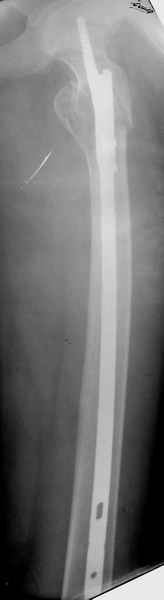

Спасибо за все ответы и комментарии по этому вопросу. Неделю назад мы прооперировали пациентку. Представляем ее снимки.

Получилось очень красиво! У меня возникло два вопроса: 1) проводилось ли выскабливание полости; 2) проводилась ли пластика?

Уважаемый Азат! Ответ на оба Ваши вопроса - отрицательный.